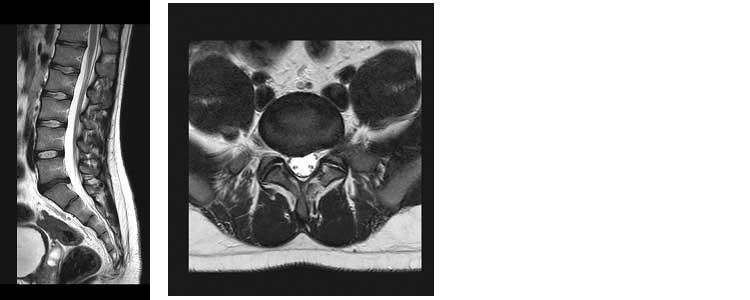

Lo studio della colonna cervicale, dorsale e lombo-sacrale risulta l’esame più richiesto in risonanza magnetica in quanto permette una ottima identificazione delle patologie discali erniarie. L’esame permette altresì una perfetta valutazione del midollo spinale. Grazie a sequenze T2 STIR è possibile evidenziare fratture vertebrali recenti.